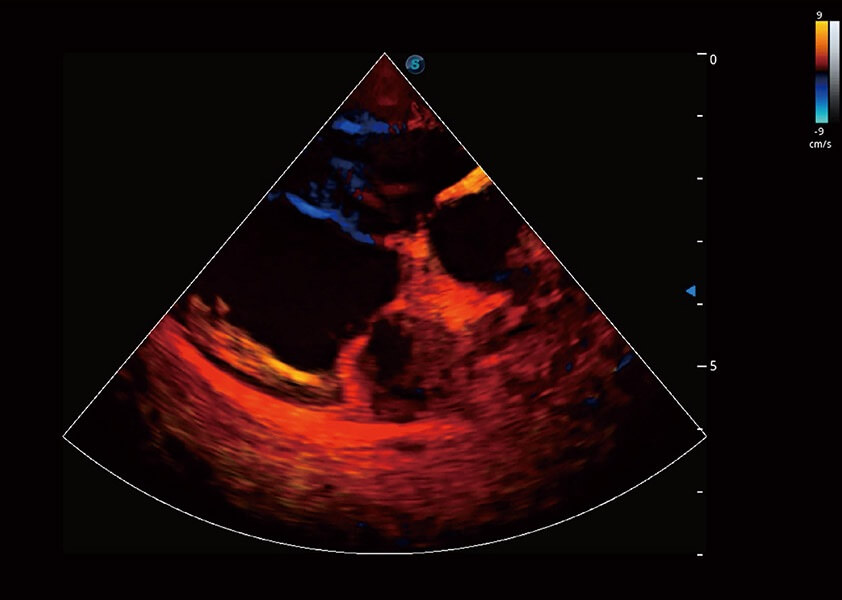

ProPet 60 作为一款高端台式动物超声设备,为动物医生的日常诊断提供了一系列贴合动物临床需求、解决临床实际问题的高级成像功能。凭借全系列高清探头,满足医生对腹部、心脏、生殖、浅表、肌骨等成像的所有需求,切实帮助您提升检查效率,提高诊断信心。

动物是人类最亲密的朋友和最值得信赖的伙伴。玖鼎集团也一直致力于探索动物专用的超声影像解决方案。 全新推出的ProPet系列,是玖鼎集团在动物超声影像智能化、专业化、精准化的一次跨越式革新。动物不能用言语来表述自己的不适,通过超声影像,ProPet系列搭建了动物医生与不同物种沟通的“桥梁”,为动物医生注入了“治愈之力”。